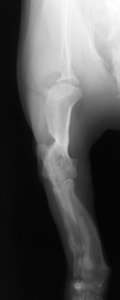

症例:トイプードル 9カ月齢

3ヵ月前より左前肢の跛行が認められるとのことで、来院されました。整形外科学的検査において、患肢の肘関節・肩関節重度の伸展制限が認められました。Xray検査において、左肩関節の内方脱臼、および肩甲骨関節窩の低形成と上腕骨頭の変形が認められました。

数か月に及ぶ慢性脱臼のため、関節面の低形成・摩耗のため整復手術による適切な再建は困難と判断し、切除関節形成術を実施しました。